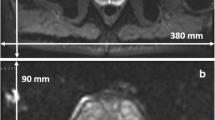

Figure 3 shows in vivo b = 800 s/mm2 single-shot and multi-shot DWIs for all pF factors and diffusion encoding waveforms. In general, for both volunteers shown, as the pF factor decreased, the signal increased due to the corresponding decrease in TE. Since the images shown in Fig. 3 are averaged images, signs of motion artefacts are not likely to be visible unless they are severe and occur frequently.

In vivo images of 2 volunteers with different partial Fourier factors for single-shot and multi-shot acquisitions at b = 800 s/mm2, averaged over repetitions and diffusion directions. All images within each volunteer have the same window level and have been cropped for better visualization. As the partial Fourier factor decreases, the signal intensity increases due to the decrease in echo time